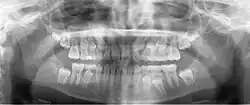

![]() Mieszane uzębienie u 9-letniego dziecka (pantomogram). | |